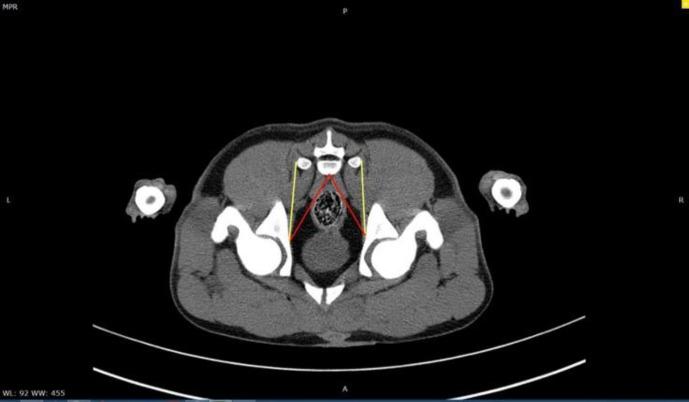

Evaluation of pelvic diaphragm muscles in dogs merits clinical attention because of the anatomical importance and their involvement in perineal hernia. This study aimed to evaluate the normal pelvic diaphragm muscles ( and coccygeus muscles) using the computed tomography (CT) scan. For this purpose, 10 male and 10 female clinically normal, adult intact mixed-breed dogs weighing 15.00 to 20.00 kg were selected randomly. All animals underwent CT examination under general anesthesia and positioned in sternal recumbency. All the CT images were taken and reconstructed with a same protocol. The measurements of the pelvic diaphragm muscles were performed based on the presented guideline to the observer. The results were presented descriptively. The mean lengths of the coccygeus muscle in CT images were evaluated 4.60 cm for males and 4.30 cm for females. The mean lengths of muscle in CT images were measured 4.90 cm in males and 4.50 cm in females. In conclusion, the results of the present study can be beneficial to clinicians and researchers for further evaluation of the supporting muscles in pelvic cavity and underlying anatomical changes in perineal hernia in dogs.

由于盆腔膈肌在解剖学上的重要性及其与会阴疝的关系,对犬盆腔膈肌的评估值得临床关注。本研究旨在使用计算机断层扫描(CT)评估正常的盆腔膈肌(和尾骨肌)。为此,随机选择了10只雄性和10只雌性临床正常、成年未绝育的体重在15.00至20.00千克之间的混种犬。所有动物在全身麻醉下接受CT检查,并采取胸骨卧位。所有CT图像均按照相同方案进行采集和重建。根据向观察者提供的指南对盆腔膈肌进行测量。结果以描述性方式呈现。CT图像中尾骨肌的平均长度,雄性为4.60厘米,雌性为4.30厘米。CT图像中肌肉的平均长度,雄性为4.90厘米,雌性为4.50厘米。总之,本研究结果可为临床医生和研究人员进一步评估犬盆腔内的支撑肌肉以及会阴疝潜在的解剖学变化提供帮助。